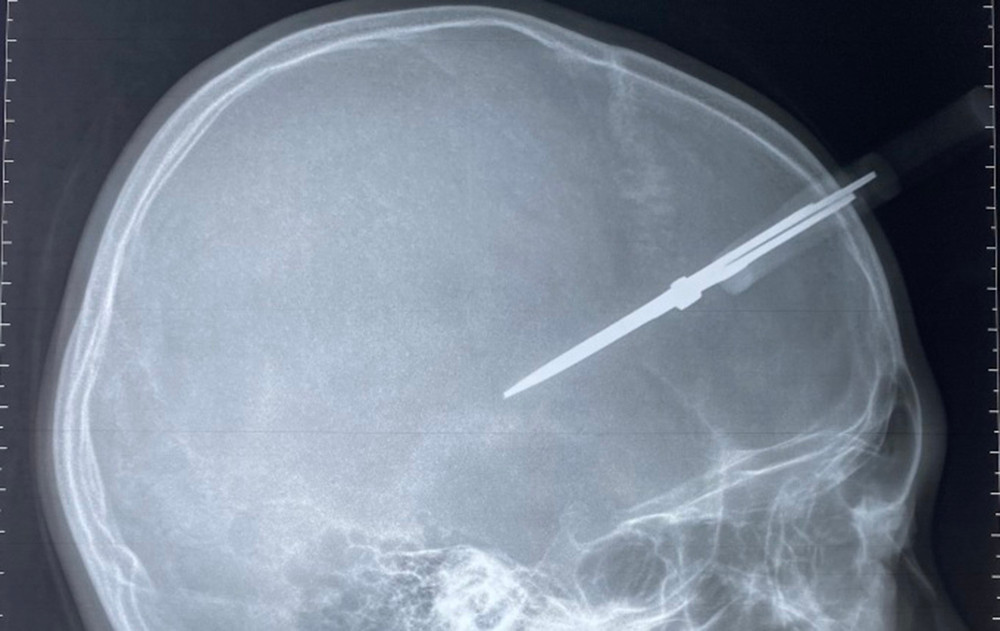

Phim chụp bé trai bị cây kéo đâm thủng hộp sọ. (Ảnh: Bác sĩ cung cấp)

Bác sĩ Trần Minh Tân, khoa Chấn thương chỉnh hình, Bệnh viện Đa khoa Đức Giang cho biết, với các trường hợp dị vật hộp sọ nguy cơ đầu tiên là chảy máu trong hộp sọ do dị vật gây rách màng não, tổn thương nhu mô não. Trường hợp này, vị trí của cây kéo nằm ở vùng thái dương, nơi có động mạch màng não giữa đi qua, rất có thể gây đứt động mạch, gây ra máu tụ ngoài màng cứng.

Theo đó, ngay sau khi có kết quả xét nghiệm, bệnh nhân được nhanh chóng chuyển vào phòng mổ. Các bác sĩ đã mở rộng vết thương, mở xương sọ, lấy bỏ cây kéo khỏi hộp sọ của bệnh nhi, làm sạch dị vật tóc, xương vụn, lấy máu tụ, cầm máu não. Sau mổ khoảng 1 giờ cháu bé đã tỉnh táo, được rút ống nội khí quản trong niềm vui mừng của gia đình và ê-kíp phẫu thuật, cháu bé tiếp tục được điều trị tích cực với hy vọng có thể được về đón Tết sớm cùng gia đình.